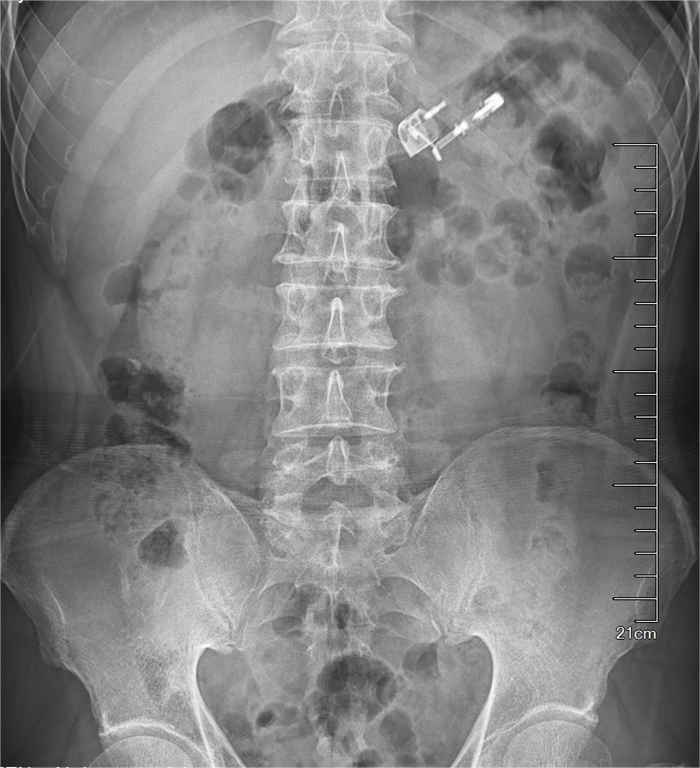

4月中旬,拉萨公安打掉一个扒窃犯罪团伙,其中一名嫌疑人为逃避法律打击吞下一个打火机,公安看守人员发现异常情况后紧急与西藏阜康医院取得联系,并把嫌疑人送到医院救治。经门诊急查腹部平片显示打火机位于胃腔内。消化内科医生沈燕如、麻醉医生邓富强、护师白央、护工白玛仓决为嫌疑人进行急诊胃镜下取异物治疗。